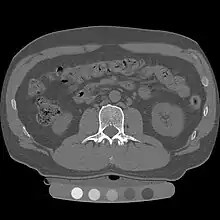

Image of cortical and trabecular bone of the spine by Quantitative computed tomography. Only the central trabecular portion is measured

At the spine, QCT is used to measure the bone mineral density of only the spongy interior bone separately from the dense cortical bone that forms the exterior walls of the vertebrae.[4] The trabecular bone has much higher metabolic activity than the cortical bone and so is affected by age, disease and therapy-related changes earlier and to a greater degree than cortical bone. This means that QCT of the spine has an advantage compared to other bone density tests because earlier changes in bone mineral density may be detected .[1]